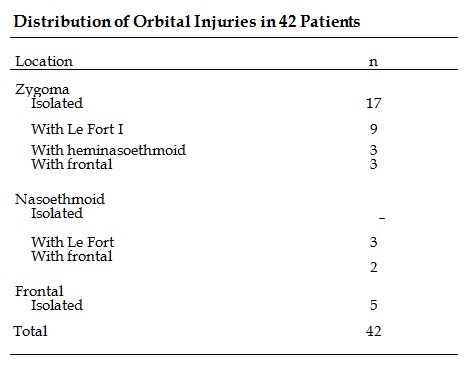

To categorize the injuries, the orbit was divided into the zygomatic, nasoethmoid, and supraorbital/frontal areas. The distribution of injuries is presented in the Table.